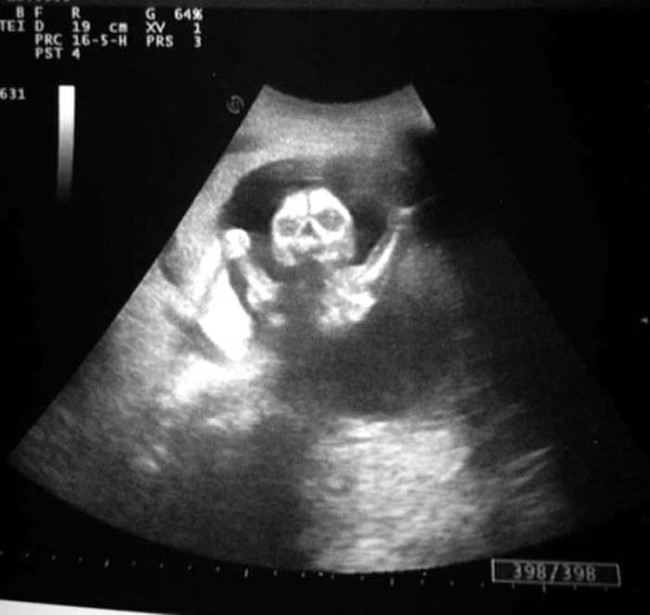

เดี๋ยวนี้ยามตั้งครรภ์คุณแม่เกือบทุกคนก็นิยมอุ้มท้องป่อง ๆ ไปให้คุณหมอทำอัลตราซาวด์ จะได้เช็กดูว่าเจ้าตัวน้อยข้างในอยู่สบายแข็งแรงดีหรือเปล่า แถมยังได้จะเห็นไปหน้าเค้าโครงใบหน้าลาง ๆ ของเจ้าหนูด้วย ดูแค่เงาก็เดาไปกันใหญ่แล้วว่าเหมือนใครมากกว่ากัน จนอดใจไม่ไหวอยากรีบคลอดออกมาให้เห็นหน้าลูกน้อยตัวจริงเร็ว ๆ แต่ถ้ามาเจอ 13 รูปอัลตราซาวด์สุดสยอง ที่เรานำมาฝากจากเว็บไซต์ boredomtherapy เหล่านี้เข้าไปหน่อยล่ะก็... บางทีคุณอาจไม่แน่ใจแล้วล่ะว่า นี่ใช่ลูกฉันจริงหรือเปล่า !!

ถึงจะรักเด็กแค่ไหน แต่ถ้าคุณขวัญอ่อนเราขอเตือนกว่าอย่าเลื่อนลงไปดูดีกว่านะ...